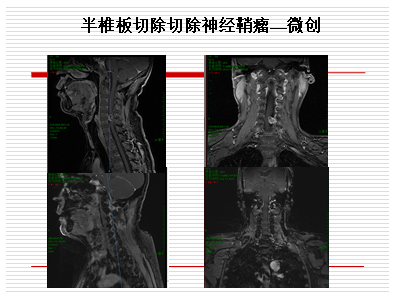

常见的椎管内肿瘤是神经鞘瘤,起源于背侧脊神经根,大多位于脊髓外硬膜内,少数可以突入椎间孔内甚至突出至椎管外呈哑铃型。脊髓神经鞘瘤首发症状常见者为神经根痛,其次为感觉异常和运动障碍。良性神经鞘瘤的治疗主要为外科手术切除。绝大多数病例均可通过标准的后路椎板切开,将载瘤神经连同肿瘤全切除,进而达到治愈。对于突出椎管外的肿瘤,尤其是椎管内体积小,颈部或胸腹腔内病变体积大的葫芦形肿瘤,通常需要联合入路。首先神经外科医生切除椎管内肿瘤,并尽量切除椎间孔内肿瘤,再从外侧入路切除椎管外肿瘤。切除肿瘤后在椎间孔处像穿山隧道一样的胜利会师,再由神经外科医生做硬膜的修补,防止术后脑脊液漏的发生。这类沟通性肿瘤手术,我科室和胸外科、头颈外科等兄弟科室合作一次手术完成。大约2.5%硬膜内脊神经鞘瘤为恶性,多数发生在多发性神经纤维瘤病患者中,预后差,通常生存期少于1年。

脊柱的承重功能是保持患者生存状态的关键,各种手术对脊柱骨结构的医源性破坏都会对脊柱稳定性产生负面影响,因此大限度减少医源性损伤和各种固定甚至重建技术在脊柱脊髓手术中发挥重要作用。对于良性神经鞘瘤等手术,可以采用半侧椎板切除、椎板切除复位固定等技术,对于骨转移癌姑息性后路减压患者可以钉棒固定来加固,椎体切除采用前路钛网钢板的内固定术,以及骨水泥充填术。